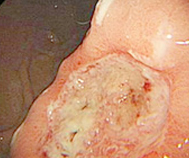

在重庆嘉华医院治愈的萎缩性胃炎患者